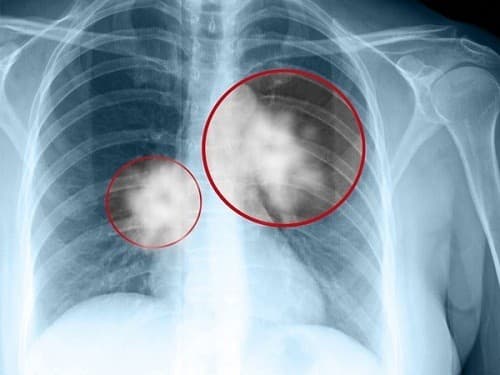

Ung thư phổi là sự phát triển không kiểm soát được của các tế bào bất thường bắt đầu ở một hoặc cả hai phổi; thường trong các tế bào lót đường dẫn khí. Các tế bào bất thường không phát triển thành mô phổi khỏe mạnh, mà nó phân chia nhanh chóng và tạo thành khối u, làm suy yếu khả năng của phổi để cung cấp máu có oxy. Ung thư phổi có thể lây lan sang các cơ quan khác, gọi là di căn.

Ung thư phổi có lây không?

Cũng giống như hầu hết các bệnh ung thư khác, ung thư phổi là bệnh không lây truyền từ người này sang người khác mà có khuynh hướng di truyền. Chẳng hạn, những người có người thân gần gũi như cha mẹ, anh chị, con cái mắc ung thư phổi, sẽ gia tăng nguy cơ mắc bệnh của người đó. Tuy nhiên, những trường hợp bị ung thư phổi do di truyền cũng chỉ chiếm 5-10%.